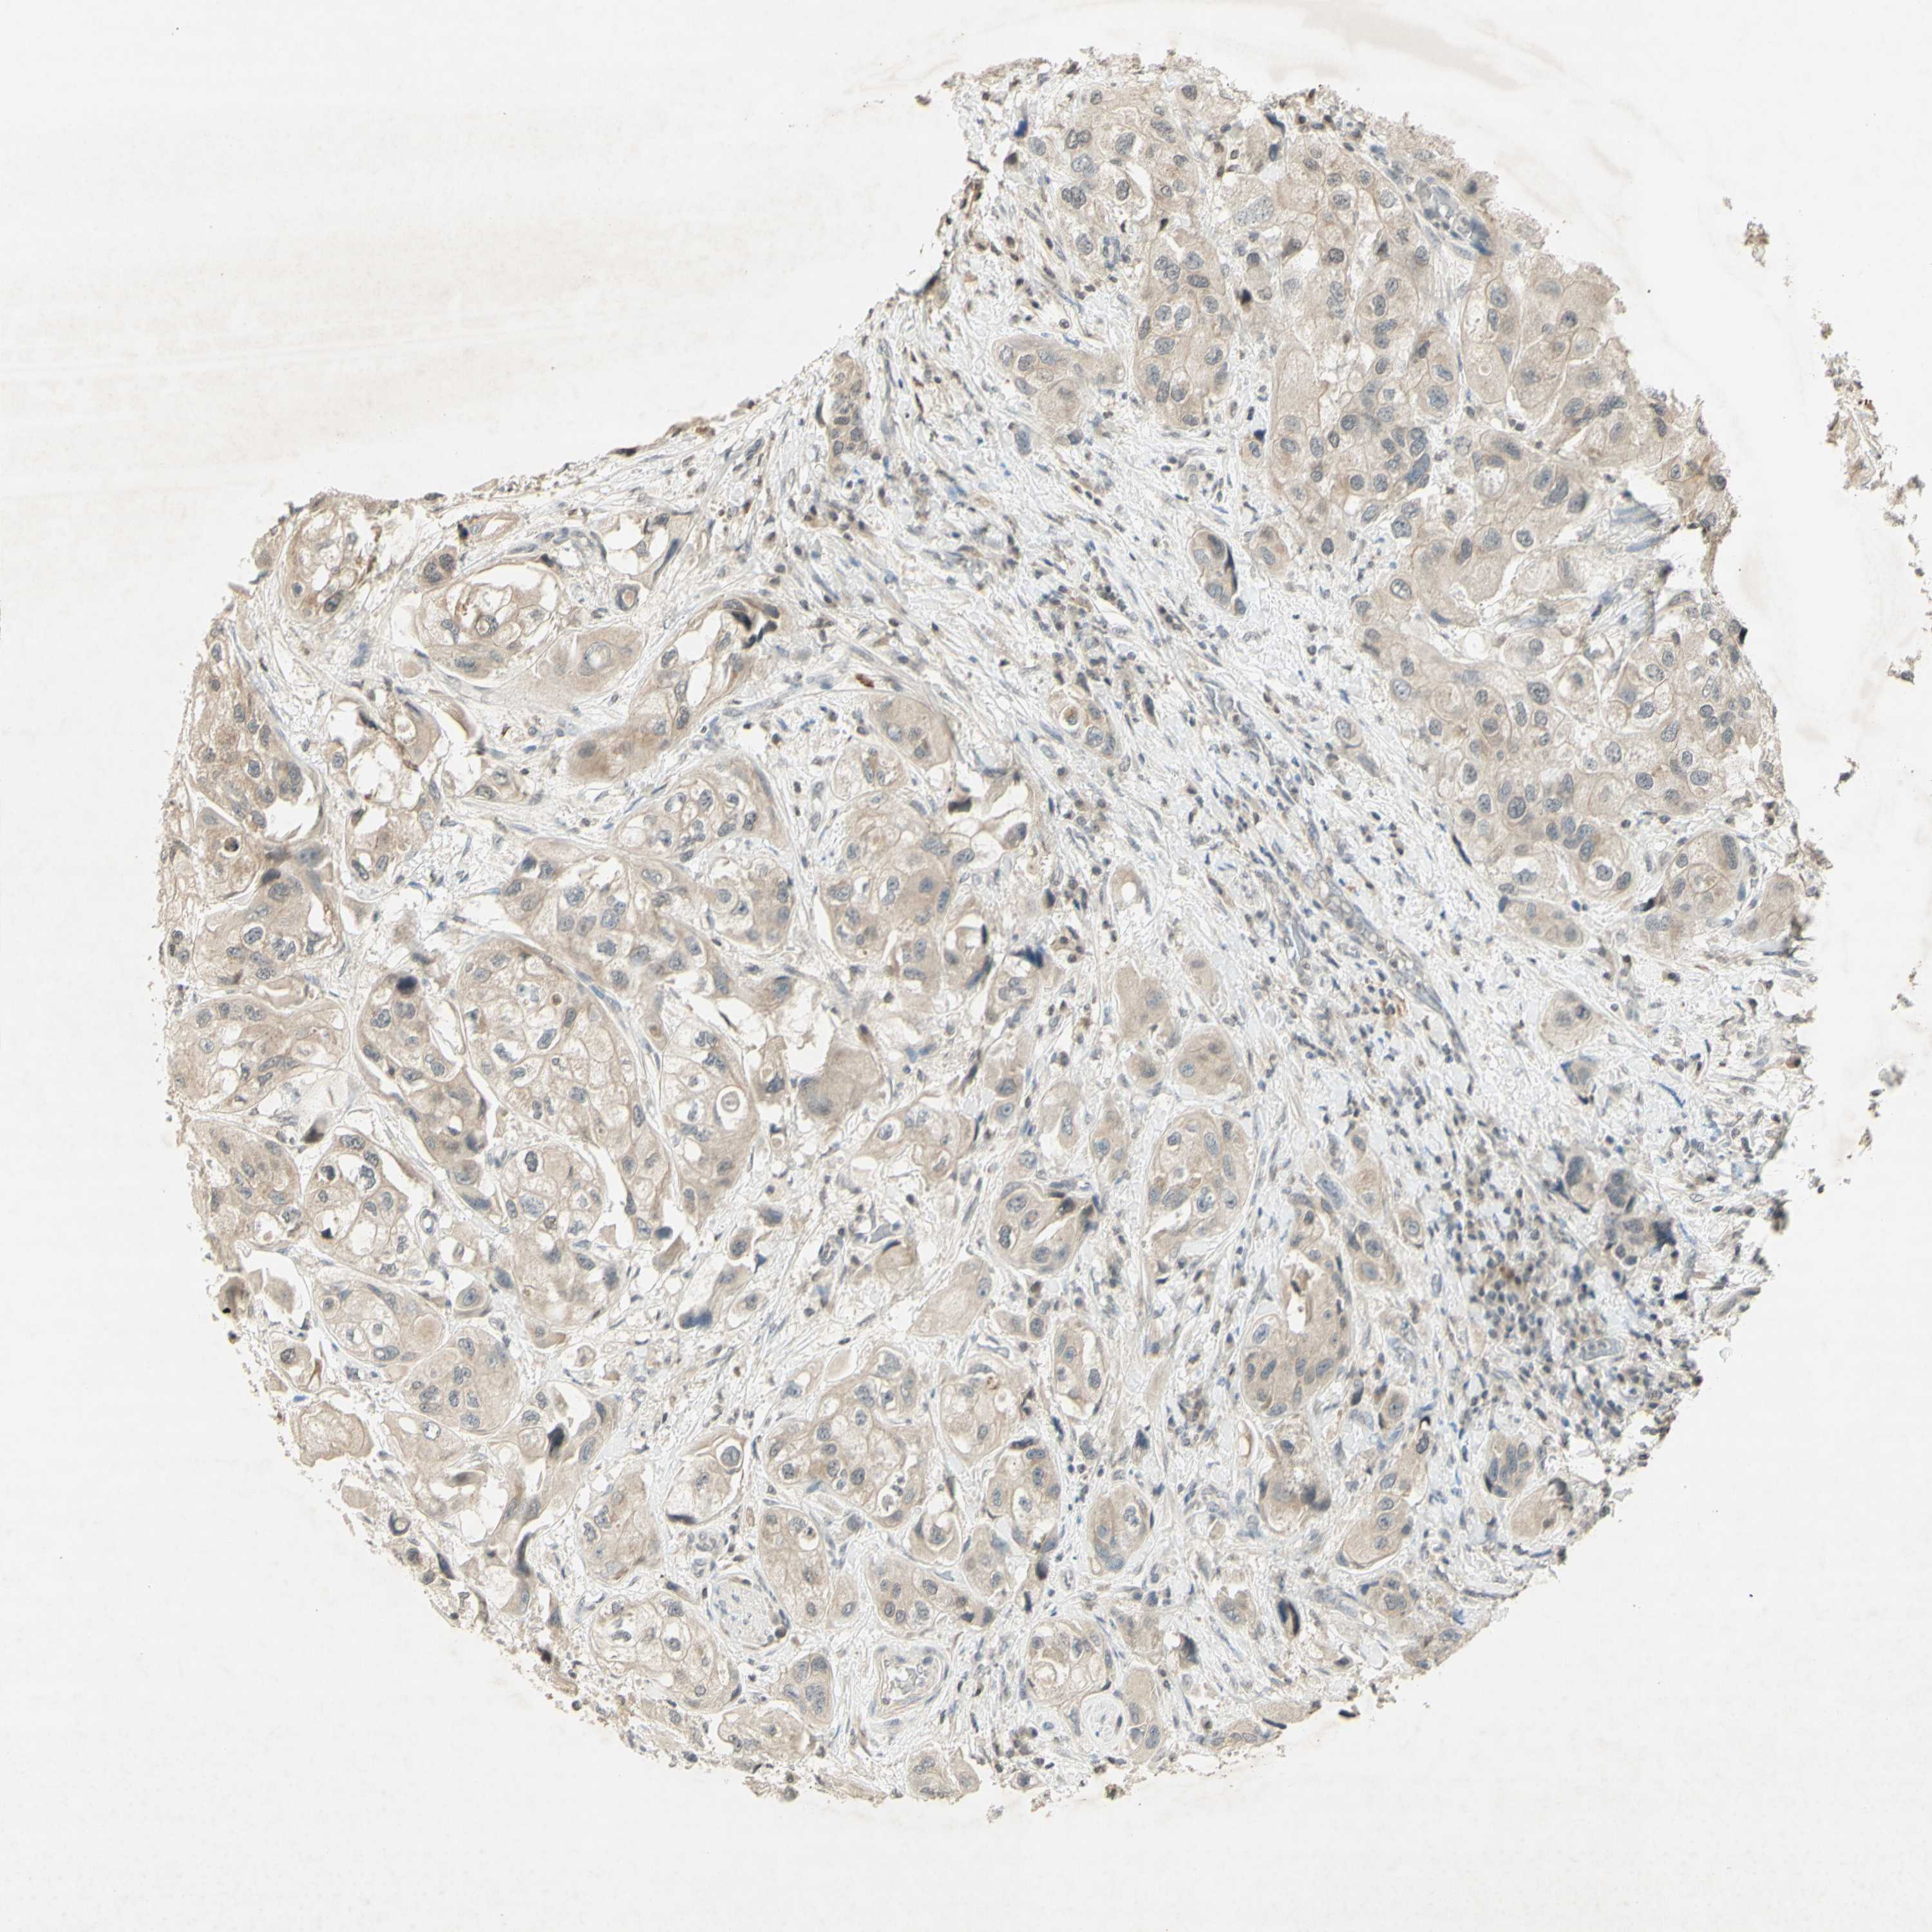

UROTHELIAL CANCER - Protein expressioni

A mouse-over function shows sample information and annotation data. Click on an image to view it in a full screen mode. Samples can be filtered based on level of antibody staining by selecting one or several of the following categories: high, medium, low and not detected. The assay and annotation is described here.

Note that samples used for immunohistochemistry by the Human Protein Atlas do not correspond to samples in the TCGA dataset.

Antibody stainingi

Antibody staining in the annotated cell types in the current human tissue is reported as not detected, low, medium, or high, based on conventional immunohistochemistry profiling in selected tissues. This score is based on the combination of the staining intensity and fraction of stained cells.

Each image is clickable and will lead to virtual microscopy that enables deeper exploration of all samples and also displays staining intensity scores, fraction scores and subcellular localization as well as patient and tissue information for each sample.

Antibody CAB009460

Staining

High

Medium

Low

Not detected

Intensity

Strong

Moderate

Weak

Negative

Quantity

>75%

75%-25%

<25%

None

Location

Nuclear

Cytoplasmic/membranous

Cytoplasmic/membranous,nuclear

Urothelial carcinoma, High grade